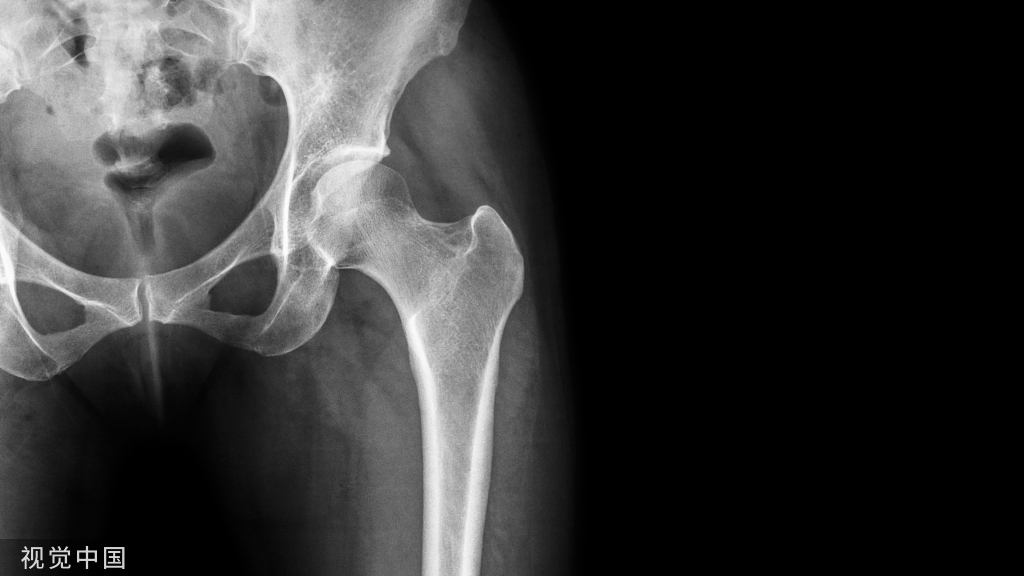

拔牙热知识:术前多读片,阻力牙才不会变压力!